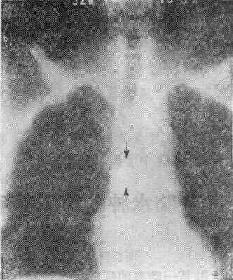

气道肿瘤(两箭头之间)

113-3 气道肿瘤(两箭头之间)

(四)占位性病变 ①血肿、脓肿是较常见的原因,如咽后壁脓肿;②肿瘤(图113-37),管腔内或管壁良恶性肿瘤错构瘤血管瘤和癌等;③气道附近组织器官的肿瘤,如甲状腺的肿瘤压迫侵犯气道。这类原因引致的气道梗阻,一般是慢性进行性的。然而当气道狭窄的程度超过管径的75%以上,由于附加因素如粘痰等可导致急性气道梗阻,产生严重的呼吸困难,甚至窒息死亡。④异物吸入气官。